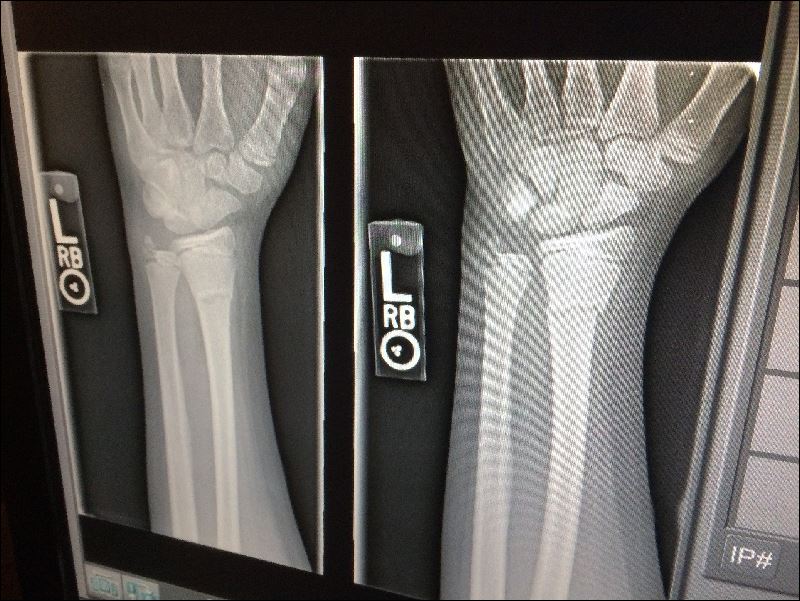

일단 척추 골절이 발생하면 재골절의 위험이 더 높아지게 됩니다.

신경이 쓰이는 증상이 있으면 그대로 두지 말고 빨리 의료 기관에서 진찰을 받읍시다.

4cm 이상 신장이 줄어든 사람은 적극적으로 골밀도 검사나 엑스레이 검사를 받도록 권장하고 있습니다.